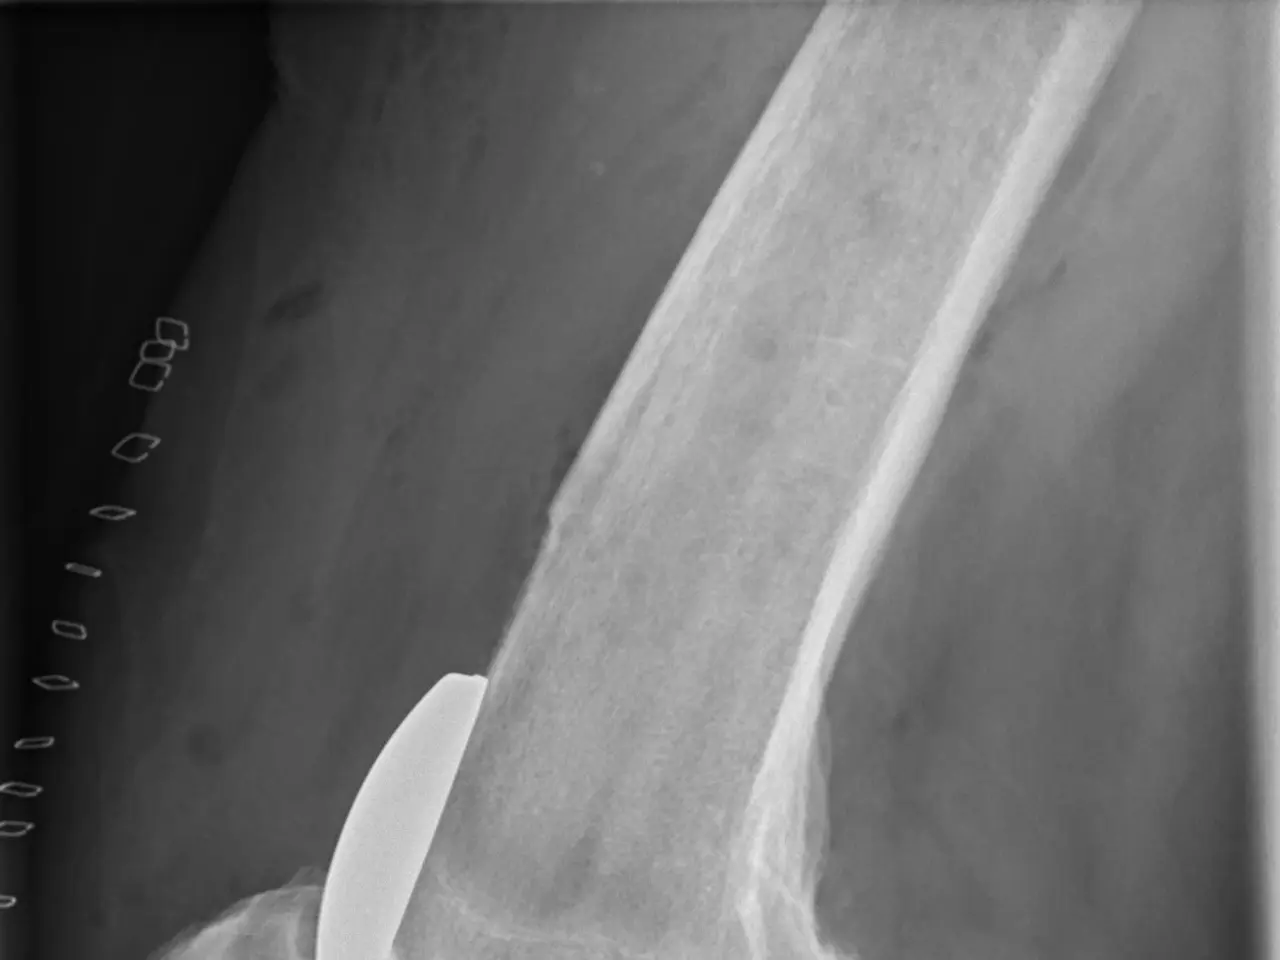

The image shows an x-ray of a human leg with a fracture in the knee, which appears to be a...

The image shows an x-ray of a human leg with a fracture in the knee, which appears to be a ligament.